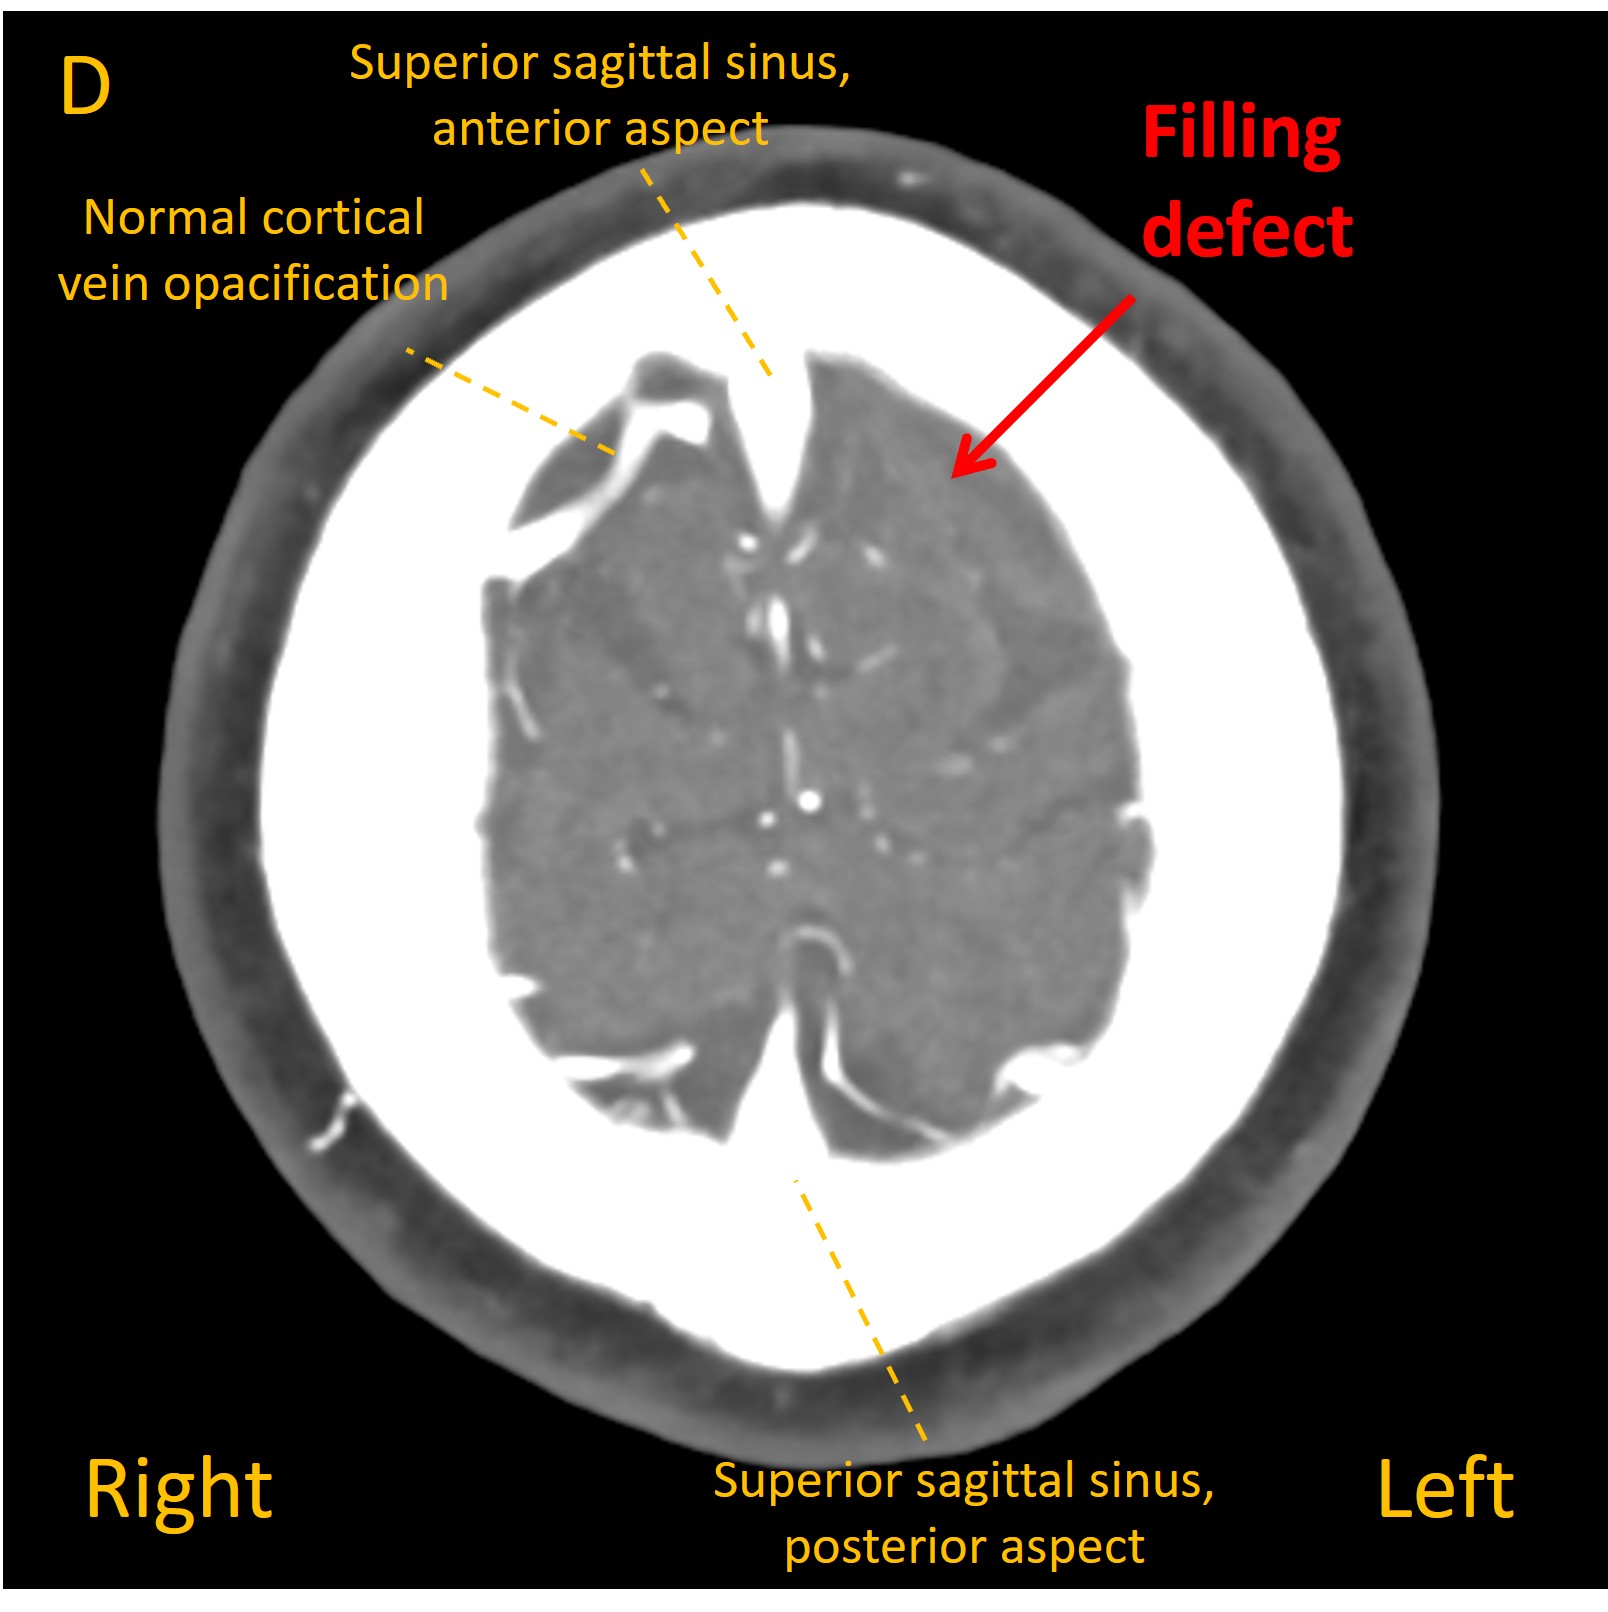

On a plain CT head a dense cortical vein was visible overlying the left frontal lobe, suggestive of static blood ( Images A and B ). A dark area of hypoattenuation was visible in the underlying brain, suggesting a venous infarction (C). Contrast venography identified a filling defect in the vein - confirming cortical venous thrombosis ( D ).